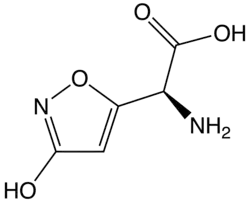

The major toxins involved in A. muscaria poisoning are muscimol (3-hydroxy-5-aminomethyl-1-isoxazole, an unsaturated cyclic hydroxamic acid) and the related amino acid ibotenic acid. Muscimol is the product of the decarboxylation (usually by drying) of ibotenic acid. Muscimol and ibotenic acid were discovered in the mid-20th century.[71][72] Researchers in England,[73] Japan[74] and Switzerland[72] showed that the effects produced were due mainly to ibotenic acid and muscimol, not muscarine.[15][71] These toxins are not distributed uniformly in the mushroom. Most are detected in the cap of the fruit, a moderate amount in the base, with the smallest amount in the stalk.[75][76] Quite rapidly, between 20 and 90 minutes after ingestion, a substantial fraction of ibotenic acid is excreted unmetabolised in the urine of the consumer. Almost no muscimol is excreted when pure ibotenic acid is eaten, but muscimol is detectable in the urine after eating A. muscaria, which contains both ibotenic acid and muscimol.[54]

Ibotenic acid and muscimol are structurally related to each other and to two major neurotransmitters of the central nervous system: glutamic acid and GABA respectively. Ibotenic acid and muscimol act like these neurotransmitters, muscimol being a potent GABAA agonist, while ibotenic acid is an agonist of NMDA glutamate receptors and certain metabotropic glutamate receptors[77] which are involved in the control of neuronal activity. It is these interactions which are thought to cause the psychoactive effects found in intoxication.[17][55]